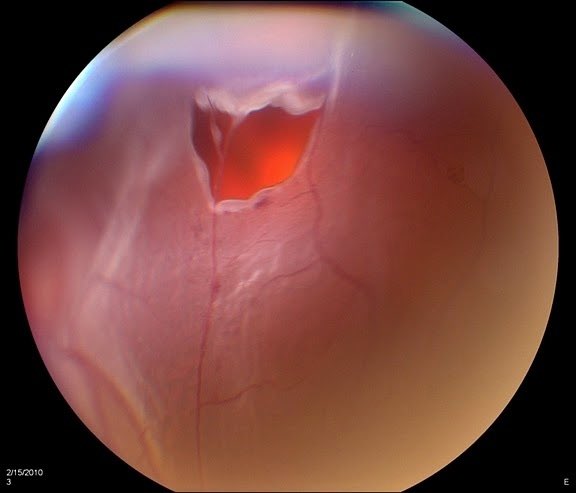

اذا استبعدنا هذي المسببات كلها وكان السبب تغيرات طبيعية في العين (انفصال السائل الزجاجي (مثل الصورة) ، او تجمّع بروتينات في السائل الزجاجي) في هذي الحالة نطمّن المراجع ان اموره طبيعية والمطلوب اهمال هذه الذبابة (يتبع)